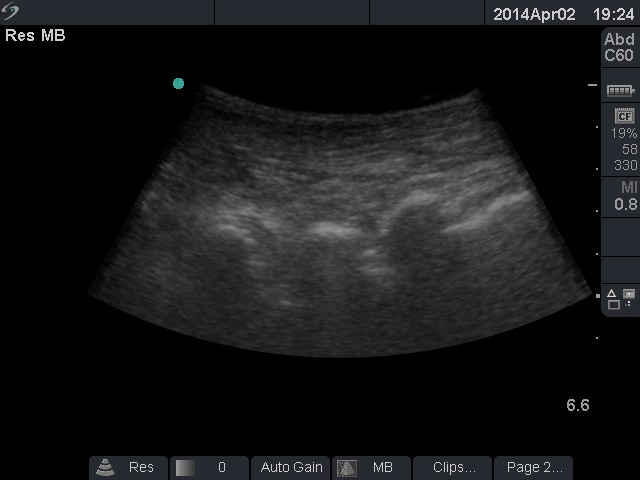

Here are some pictures showing the space we are looking for. Once the sacrum is identified, you can localize the L3-L4, L4-L5 and L5-S1 intervertebral spaces. Under direct view, with the probe in the paramedian oblique sagittal plan, just guide your needle into the interlaminar space.

4- Move the probe few centimeters away from the midline and sweep the beam toward the vertebral canal to obtain a paramedian oblique sagittal view. You will see something that looks like the median sagittal view, but the bones are deeper. These bones are the laminae. The needle should be guided in the interlaminal space.